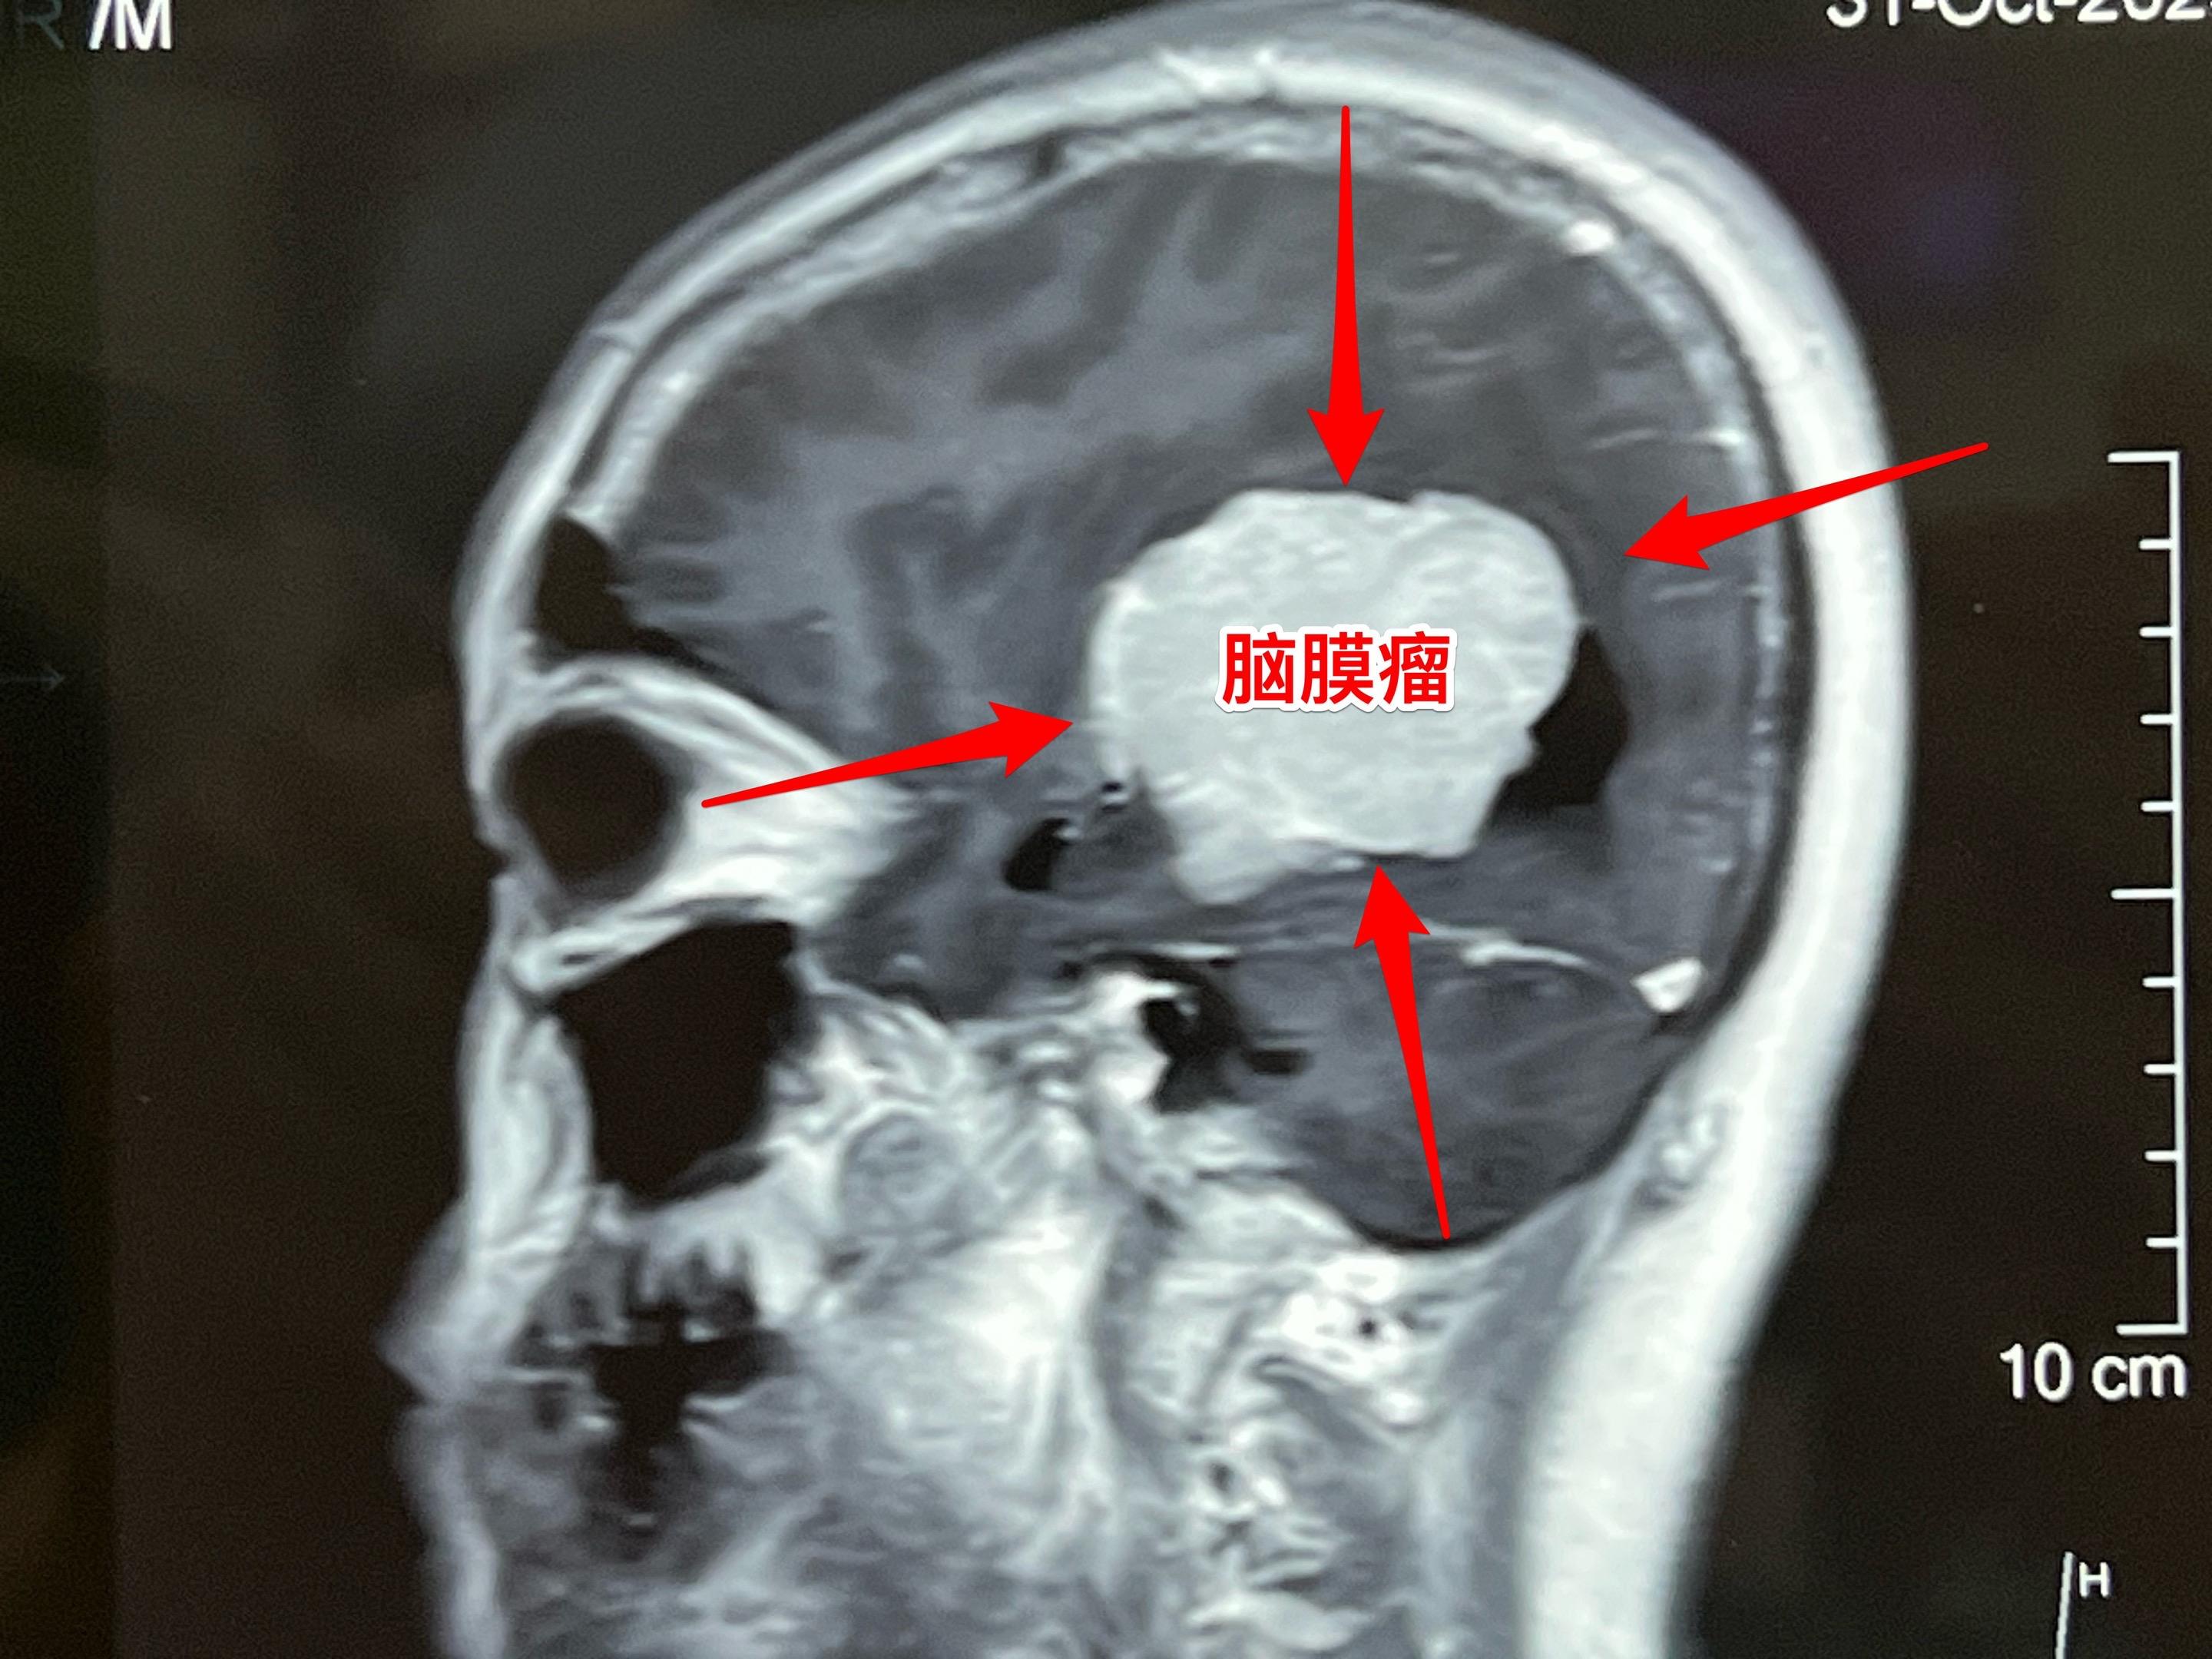

脑室内脑膜瘤也是良性肿瘤。49岁朝鲜族女性,在韩国工作,因头痛、呕吐发现这个肿瘤,随即回国治病。 这个肿瘤位于右侧脑室的三角区,脑室内的脑膜瘤最好发于这个位置。如果作手术彻底切除这个肿瘤,可以获得治愈。